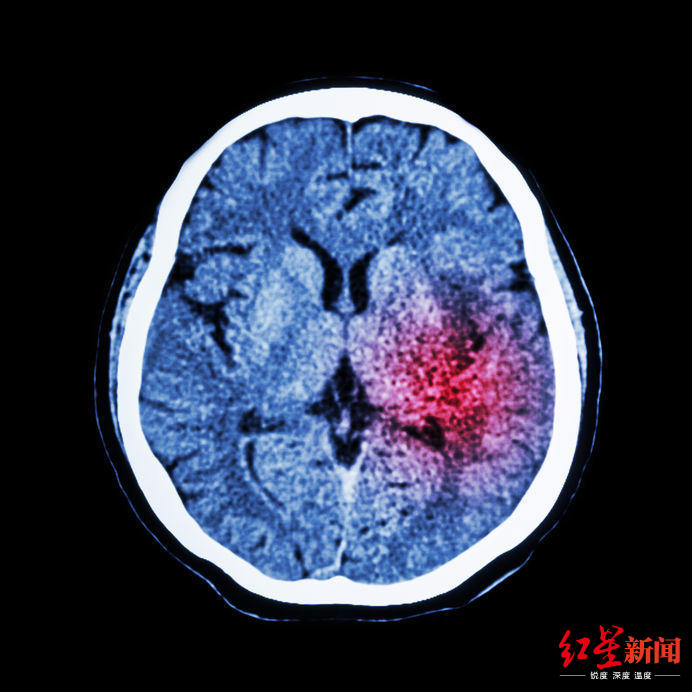

医疗射线带来的辐射属于电离辐射,电离辐射携带巨大的能量,能对人体DNA造成损伤。

普通人一年接受的电离辐射上限是1个单位。

医疗照射辐射:

胸片0.02 mSv;头颅CT < 2mSv;

胸部CT < 4mSv;

腹部CT < 6mSv。

所以,只要不是天天做放射检查,就没有必要对X光、CT过度焦虑,而且,设备越好,辐射的剂量越低,去正规医院没错的。

伍兵教授说,对已经得了病的患者来说,接受医疗辐射的副作用和忍受生病的痛苦是一个两害相权取其轻的过程,医疗照射不是核灾难,是医生基于健康,权衡利弊后做出的选择,不该过度恐慌。